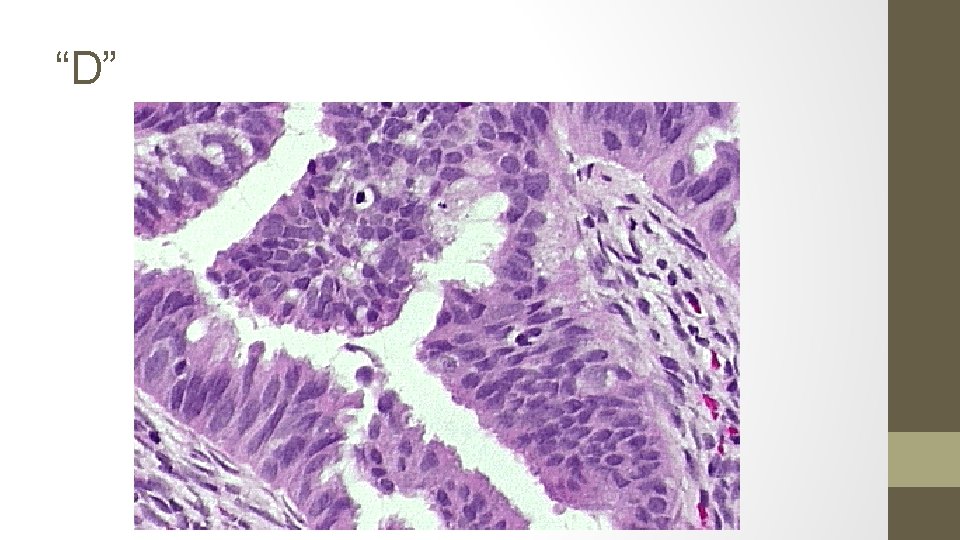

15. The biopsy samples get mixed up, the pathologist takes stress leave and you are presented with the following 5 results. Identify each smear.

A. Simple hyperplasia, no atypia (1% progression to ca) B. Complex hyperplasia, with ATYPIA (29%) C. Endometrial carcinoma (100%) D. Complex hyperplasia, no atypia (3%) E. Simple hyperplasia, with ATYPIA (8%)

Complex hyperplasia o o o Extensive glandular crowding Architextural complexity The cells lining this complex gland are pseudostratified. The nuclei are elongated and hyperchromatic. Nucleoli are not prominent. The cells retain in general their orientation to the lumen. No Atypia With Atypia o o Nuclear enlargement (elongated, hyperchromatic) Nucleoli are prominent Variation in nuclear size and shape Atypical mitosis TREATMENT OF ENDOMETRIAL HYPERPLASIA NO ATYPIA Low dose Progestins MPA 10 mg qd x 6 months High dose progestins MPA 200 qd Megestrol acetate 160 qd Micronized progesterone 200 qd Mirena WITH ATYPIA Hysterectomy & BSO High dose progestins Mirena EMB q 3 -6 MONTHS

Endometrial carcinoma o. Crowded glands, with little or no stroma o. Stromal inflammatory reaction surrounding endometrial gland o. Malignant nuclei (by HPF): round, course, chromatin clumping